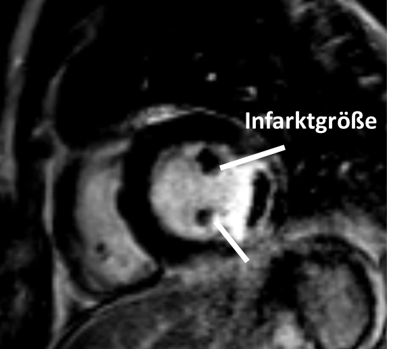

Zusätzlich wird in der klinischen Routine das CMR zum Vitalitätsnachweis nach einem akuten oder chronischen Myokardinfarkt eingesetzt. In Abhängigkeit von der Ausdehnung der Myokardnarbe (transmural vs. subendokardial) können weitere therapeutische Maßnahmen abgeleitet werden (konservatives Procedere oder Herzkatheteruntersuchung).

Herzinfarktdarstellung